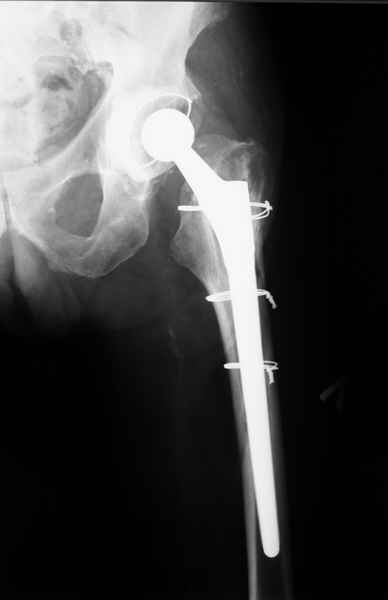

Уважаемые коллеги, продолжая дискуссию, начатую на "Вреденовских чтениях", хочу сказать, что принципиально сущестует два возможных варианта лечения.

1.Остеосинтез на ножке. Мне кажется, что применительно к этому случаю малоперспективный вариант. Синтез хорош, когда можно его выполнить в малоинвазивном исполнении и достигнуть стабильности. Действительно, если ножка б/цементной фиксации после этого не будет иметь фиксации, то ревизия не будет иметь проблем. В представленном случае стабильность синтеза сомнительная, а проведение доп.иммобилизации приведет к контрактуре суставов.

2. Применение ножки дистальной фиксации, мы отдаем предпочтение ножке Вагнера с фиксацией проксимального отдела на ножке. Более травматичное вмешательство, но при стабильной фиксации ножки реабилитация идет в обычном режиме.

Хочется показать два подобных случая, П-ка З. 72 лет и п-т Г. 80 лет. Сразу принимаю замечание, что это были ножки цементной фиксации, просто под руками не было бесцементника.